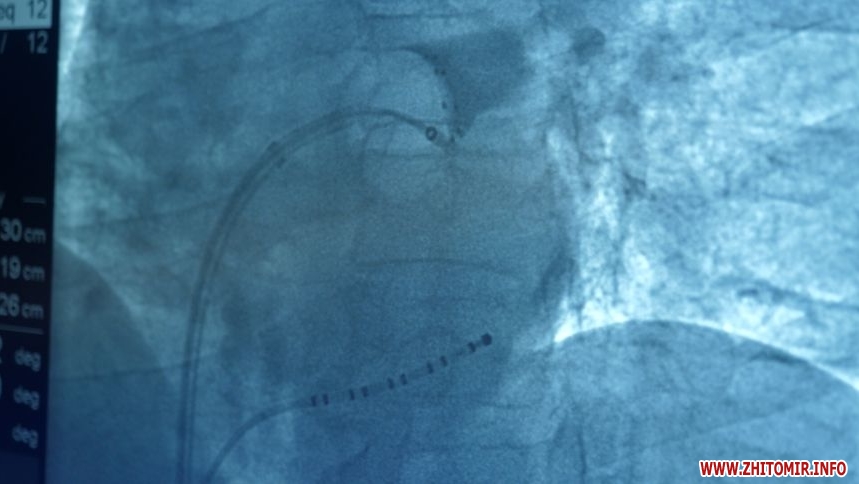

«Ми вперше провели операцію кріобалонної ізоляції легеневих вен. Кожна операція тривала близько двох годин, це пов'язано з тим, що ми цю операцію робили вперше і потрібні були певні технічні моменти. І на саму операцію було залучено близько п'яти людей. Це обладнання, яке дає змогу зробити електричний бар'єр, щоб патологічні електричні імпульси із легеневих вен не потрапляли в пересердя та не викликали аритмію. Ця операція впливає саме на якість життя. Термін життя не продовжує, а вплинути на якість життя», – говорить лікар-кардіолог Микола Кушнір.